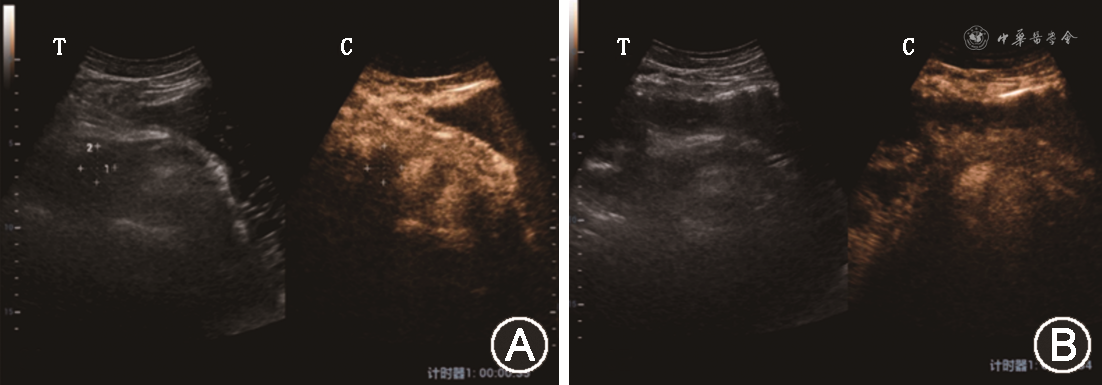

3. 治疗前首次就诊时胰腺超声造影表现:(1)17例胰腺弥漫性受累者中,有9例胰腺整体在增强早期、增强晚期、延迟期依次表现为稍低增强-低增强-低增强(图1),有5例在增强早期、增强晚期、延迟期依次表现为等增强-低增强-低增强(图2),有3例在增强早期、增强晚期、延迟期依次表现为稍高增强-低增强-低增强;(2)37例胰腺局灶性受累者中,有25例病灶在增强早期、增强晚期、延迟期均表现为低增强-低增强-低增强(图3),7例在增强早期、增强晚期、延迟期均表现为等增强-等增强-等增强(图4),2例在增强早期、增强晚期、延迟期依次表现为稍高增强-低增强-低增强,3例在增强早期、增强晚期、延迟期依次表现为稍高增强-等增强-等增强。

37例胰腺局灶性受累者中:(1)共有21例患者治疗后在增强早期-增强晚期-延迟期3期中至少有1期出现了造影强度的增高,其中有15例患者由治疗前的低增强-低增强-低增强变为治疗后的等增强-等增强-等增强(图6),4例由治疗前的低增强-低增强-低增强变为治疗后的高增强-低增强-低增强,1例由治疗前的稍高增强-低增强-低增强变为治疗后的稍高增强-稍低增强-稍低增强,1例由治疗前的稍高增强-低增强-低增强变为治疗后的稍高增强-等增强-等增强;(2)共有16例患者治疗前后在造影强度上没有发生变化,其中有6例在治疗前后均表现为低增强-低增强-低增强,7例在治疗前后均表现为等增强-等增强-等增强,3例在治疗前后均表现为稍高增强-等增强-等增强。